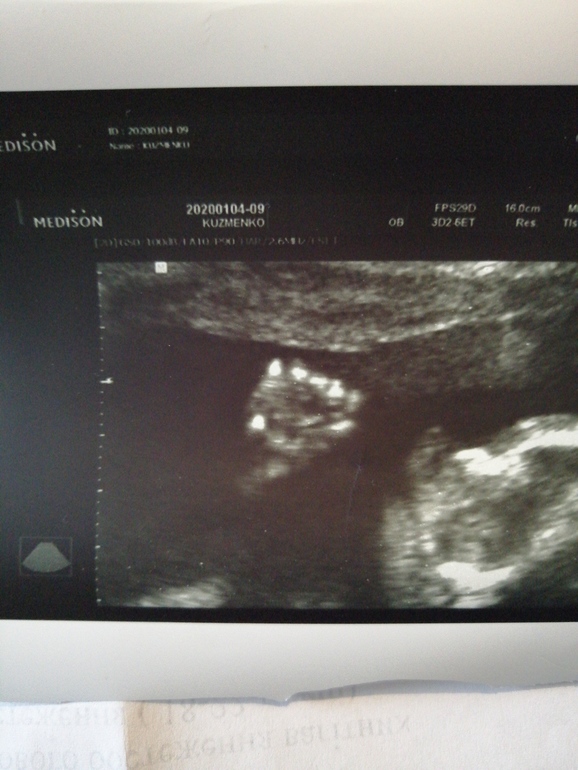

Мой внеплановый поход на узи (фото)

УЗИ, КТГ, доплерВрачи говорила контролировать тяж и ходить переодически на узи , сегодня как раз и решила сходить))) Аришка заметно подросла, догнали по срокам, ранее опаздывала на недельку почти, весит мой пузяш маленький уже 470 грамм, а самое радостное и важное ПРОПАЛ ЭТОТ АМНИОТИЧЕСКИЙ ТЯЖ🤗🤗🤗🎉🎉🎉🎉🥳🥳🥳🌼 Я довольна и спокойна😍🥰😊Ну и фоточки моей бубочки, 22 недели и 3 дня